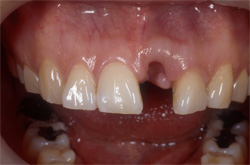

| 従来は局部的な入れ歯を用いて治療を行っていましたが、インプラントを何本か用いて治療を行います。入れ歯を固定するための金属のバネによる違和感がなくなります。 |

| 数本のインプラントにより支えられるブリッジかクラウンにより、機能と顔立ちが回復するでしょう。 |